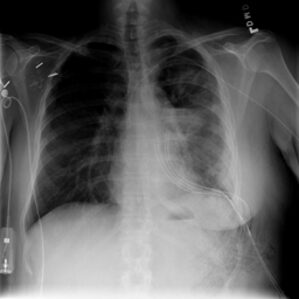

COVID-19 Radiography Database Chest X-ray Image Database

The COVID-19 Radiography Database is a chest X-ray image database created by researchers from Qatar University, Dhaka University, and other countries in collaboration with doctors. This database contains images of COVID-19 positive cases, normal conditions, and viral pneumonia to help researchers conduct research during the COVID-19 pandemic.

The dataset contains 3,616 COVID-19 positive cases, 10,192 normal cases, 6,012 lung opacity (non-COVID-19 lung infection) cases, and 1,345 viral pneumonia images and corresponding lung mask images.